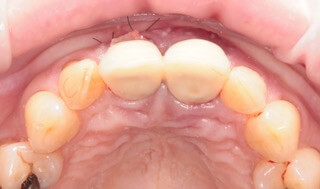

Do známeho českého časopisu Implants sme prispeli kapitolou, v ktorej Dr. Michal Repaši popisoval klinický prípad navigovanej chirurgie z praxe. Išlo o 45 ročnú pacientku, ktorá sa obrátila na našu kliniku s bolesťou v oblasti horných stredných rezákov. Pri dôkladnom vyšetrení a CT diagnostike bola v oblasti zuba č. 11 zistená vertikálna fraktúra koreňa. V oblasti zuba č. 21 palatinálne bol prítomný hlboký kaz koreňa.

Ideálnym riešením teda bola náhrada zubov implantátmi spolu s nasadením koruniek, a to počas jedného sedenia. V deň konzultácie bol pacientke urobený sken pomocou intraorálneho skeneru 3Shape TRIOS, ktorý nám umožňuje zobraziť 3D simuláciu ústnej dutiny. Pomocou softwaru 3Shape Implant Studio sme spojili dáta z intraorálneho skenu a CBCT, STL a DICOM súbory.

V ďalšom kroku sme virtuálne vložili implantáty v správnej protetickej polohe, navrhli šablónu pre ich zavedenie, namodelovali individuálne abutmenty a korunky. Kompletné dáta sme exportovali pre frézovanie a 3D tlač. V laboratóriu sa pomocou 3D tlačiarne vytlačila chirurgická šablóna, ktorá nám slúži na presné zavedenie implantátov – použili sme implantačný systém Dentium Super Line. Následne boli vyfrézované zirkonové abutmenty a plastové dočasné korunky.

Ukážka - navigovaná chirurgia z praxe